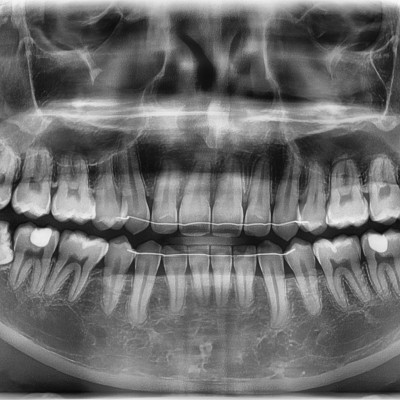

#28,38 사랑니 발치 #28,38 사랑니 발치 구강 외과 전문의가 당일 발치했습니다. ------------------------..